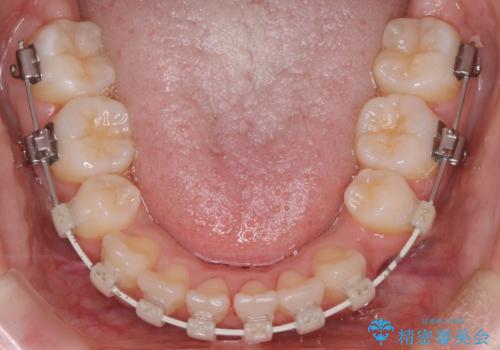

- 4番の歯を4本抜歯をし、上顎にマイクロインプラントを2本埋入し、遠心移動を行いました。

主訴のオープンバイトは改善し、抜歯をしたことで前歯が下がり綺麗になりました。抜歯矯正でしたが1年2か月という短い期間で終了しました。